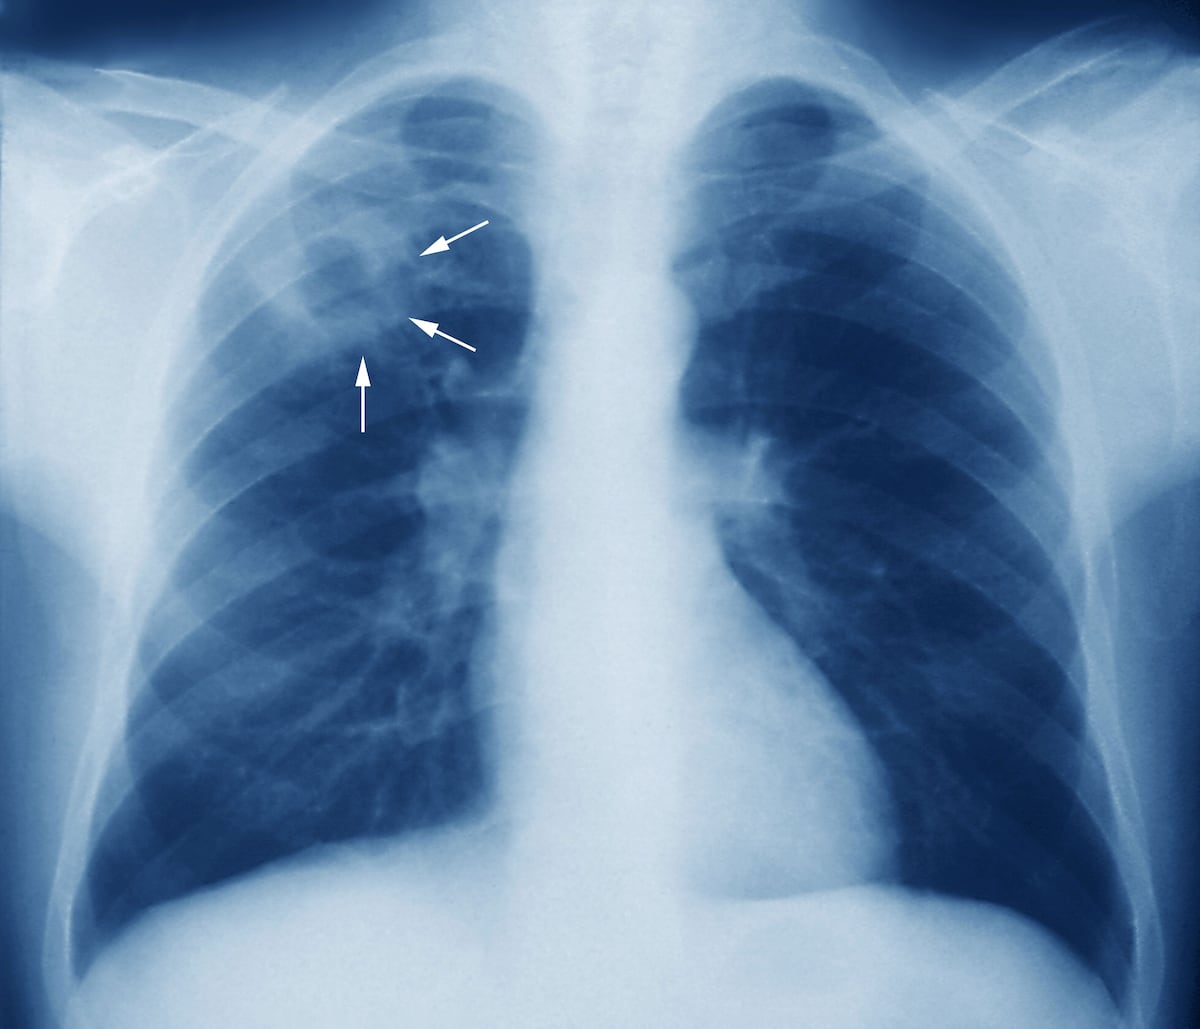

Desde el 2017 Panamá trabaja en la estrategia de buscar los pacientes sintomáticos respiratorio que son los pacientes que presentan tos por más de 15 días, se les realiza la prueba de baciloscopia o la prueba Xpert para detección molecular.